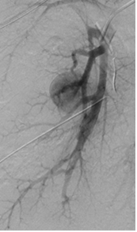

Cas 2 : Pseudo-anévrysme sur branche sous-segmentaire de l’artère pulmonaire droite

après multiples drainages pour infection pleuro-pulmonaire sévère. Contrôle avant et après

embolisation par coil.